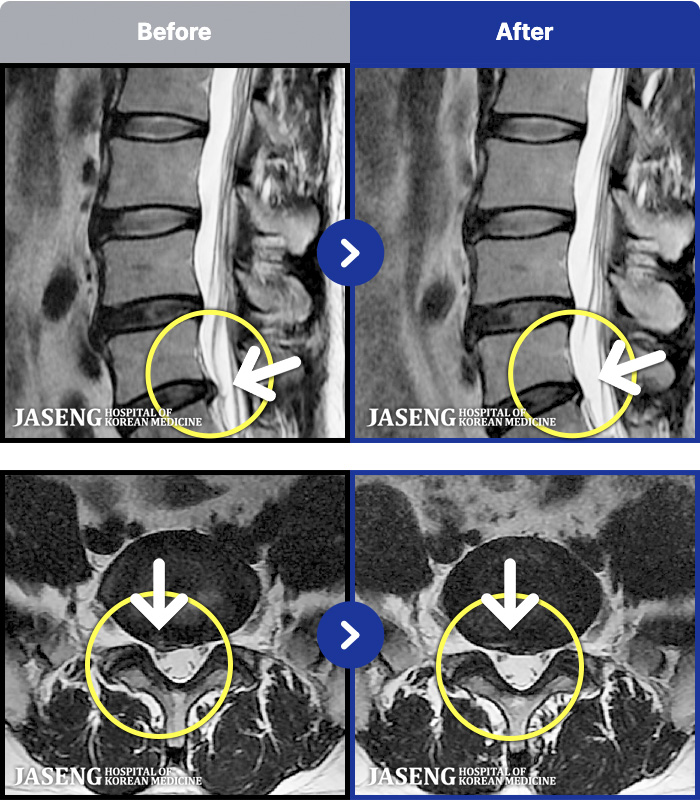

1,286 MRI ũ ʸ Ȯϼ.